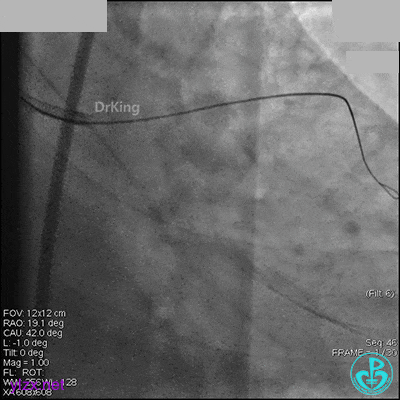

AL 1.0指引导管到位,简单短时尝试导丝不能顺利通过前降支或回旋支病变。改变策略处理右冠脉病变,计划植入2枚支架。AL指引导管到位,Sion blue导丝到达右冠脉远端。导丝通过后1.5mm及2.5mm球囊14~16atm充分扩张中段病变。

右冠脉中段充分扩张后欲植入3.5×38mm支架时,支架难以通过中远段扭曲处,且指引导管、导丝弹出飞扬。反复尝试导丝重新到达右冠脉远端时通过不顺利,局部造影剂滞留,远端血流接近3级。

右冠脉血流3级,患者无症状,终止手术。